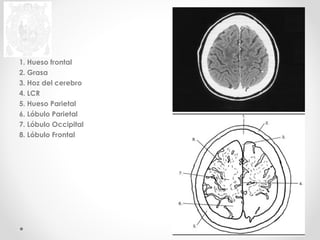

1. Hueso frontal

2. Grasa

3. Hoz del cerebro

4. LCR

5. Hueso Parietal

6. Lóbulo Parietal

7. Lóbulo Occipital

8. Lóbulo Frontal